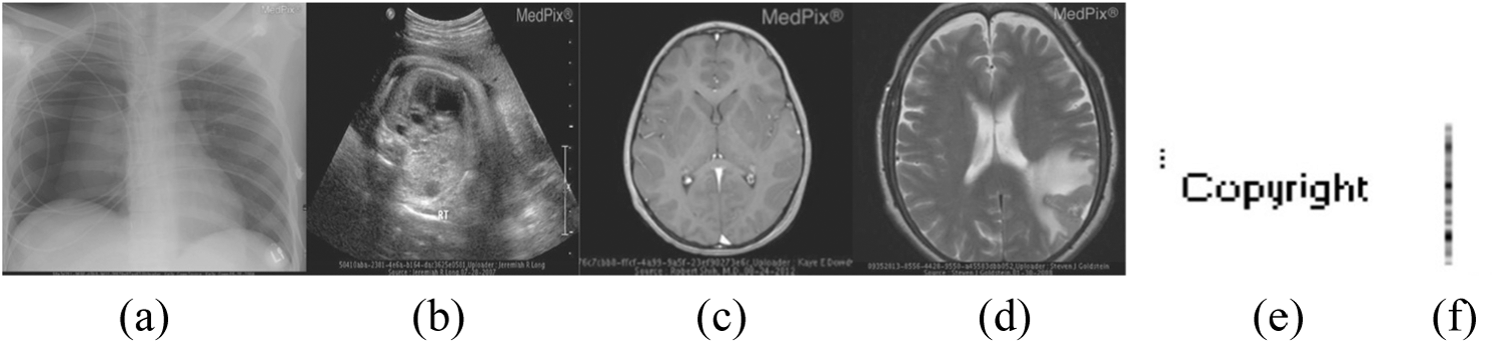

The proficiency of the proposed EbHFT technique is examined on medical images dataset which involves Magnetic Resonant Imaging (MRI), Computerized Tomography (CT), X-ray, and Ultrasound (US) collected from the MedPixTM Medical Image Database [35]. Images included in the experiment are all of resolution

Figure 3: Host medical images: (a) X-ray (b) Ultrasound (US) (c) Magnetic Resonant Imaging (MRI) (d) Computerized Tomography (CT), (e) The ‘Copyright’ watermark image and (f) The embedding key

The JPEG compression is implemented on the watermarked images along with several quality criteria. At End, the watermark is extracted using the proposed technique. In Tab. 3, the results of compression attacks are presented for distinct medical images (i.e., displayed in Figs. 3a–3d) involving X-rays, Ultrasound, MRI and CT images. These images are accompanied with a watermark logo (i.e., Fig. 3e) and NC to appraise the compression attacks against these images. The conducted results evidence the outperforming of the EbHFT technique. Same selected watermarked images are exposed to diverse sorts of noise attacks such as speckle, salt-and-pepper noise, and Gaussian noise. NC for these attacks and the outcomes are exhibited in Fig. 6. Fig. 7 shows the results of applying filtering attacks (i.e., such as median mean and Gaussian low pass filtering).